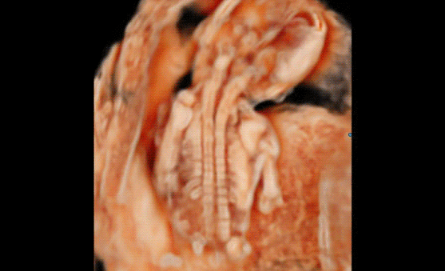

3D/4D成像方面,Hera i 10通過結(jié)合先進(jìn)的圖像渲染技術(shù),著重加強了邊緣和小結(jié)構(gòu)的可視化能力。